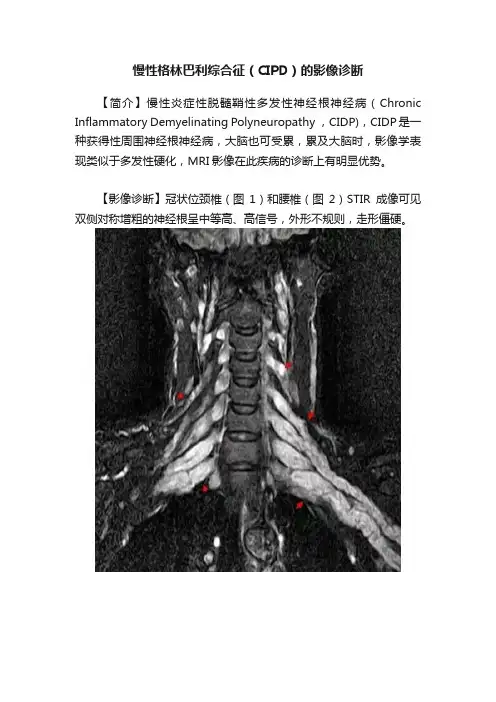

【简介】慢性炎症性脱髓鞘性多发性神经根神经病(Chronic Inflammatory Demyelinating Polyneuropathy ,CIDP),CIDP是一种获得性周围神经根神经病,大脑也可受累,累及大脑时,影像学表现类似于多发性硬化,MRI影像在此疾病的诊断上有明显优势。

【影像诊断】冠状位颈椎(图1)和腰椎(图2)STIR成像可见双侧对称增粗的神经根呈中等高、高信号,外形不规则,走形僵硬。